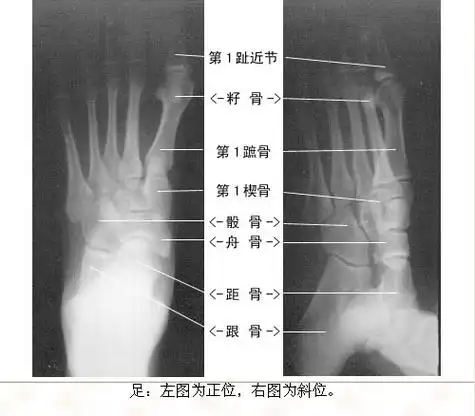

发几张正常x线片

生动,易懂 x线检查 踝关节正侧位摄片 足正斜位摄片